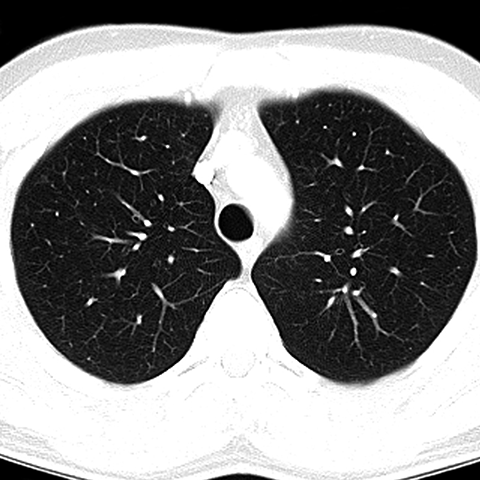

CT of Normal Trachea and Bronchi [2 of 5]